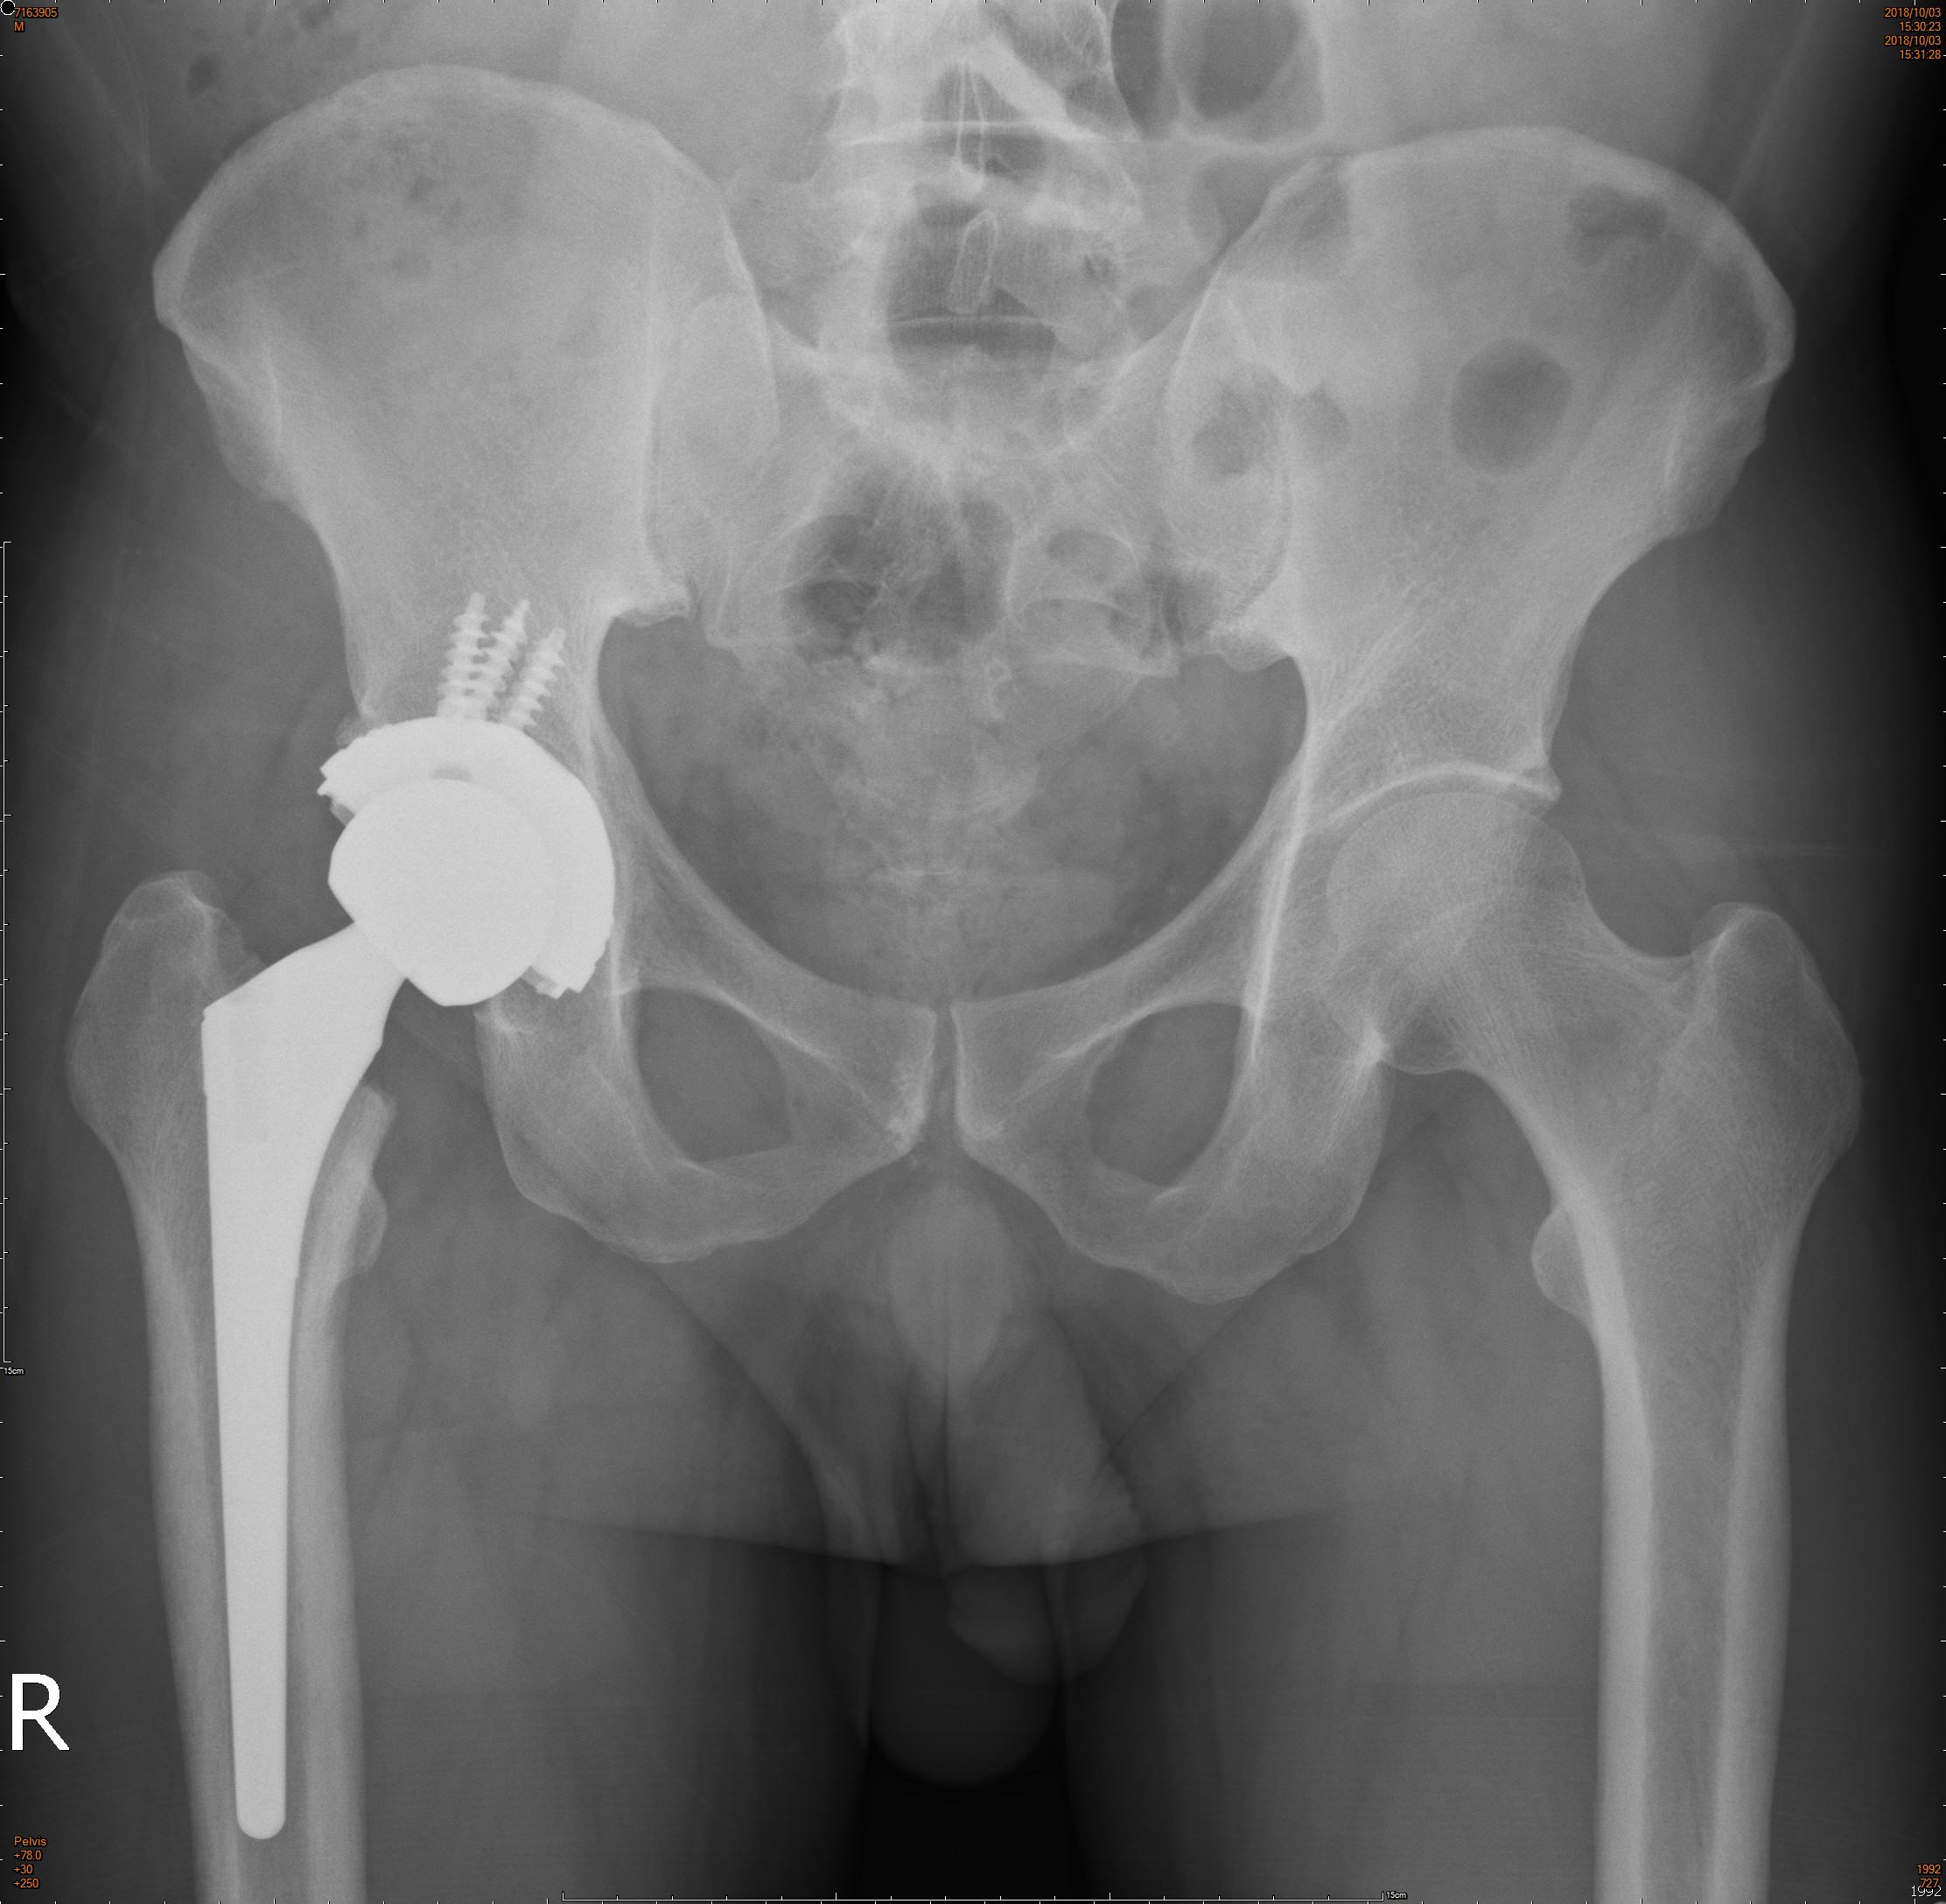

3. 人工髖關節置換:當塌陷的範圍太大或是影響關節而形成關節炎時,可能就需要使用人工髖關節置換來治療。手術會將壞死的部位切除,並裝上人工關節以期恢復活動度及改善生活品質(圖三)。

(圖三)